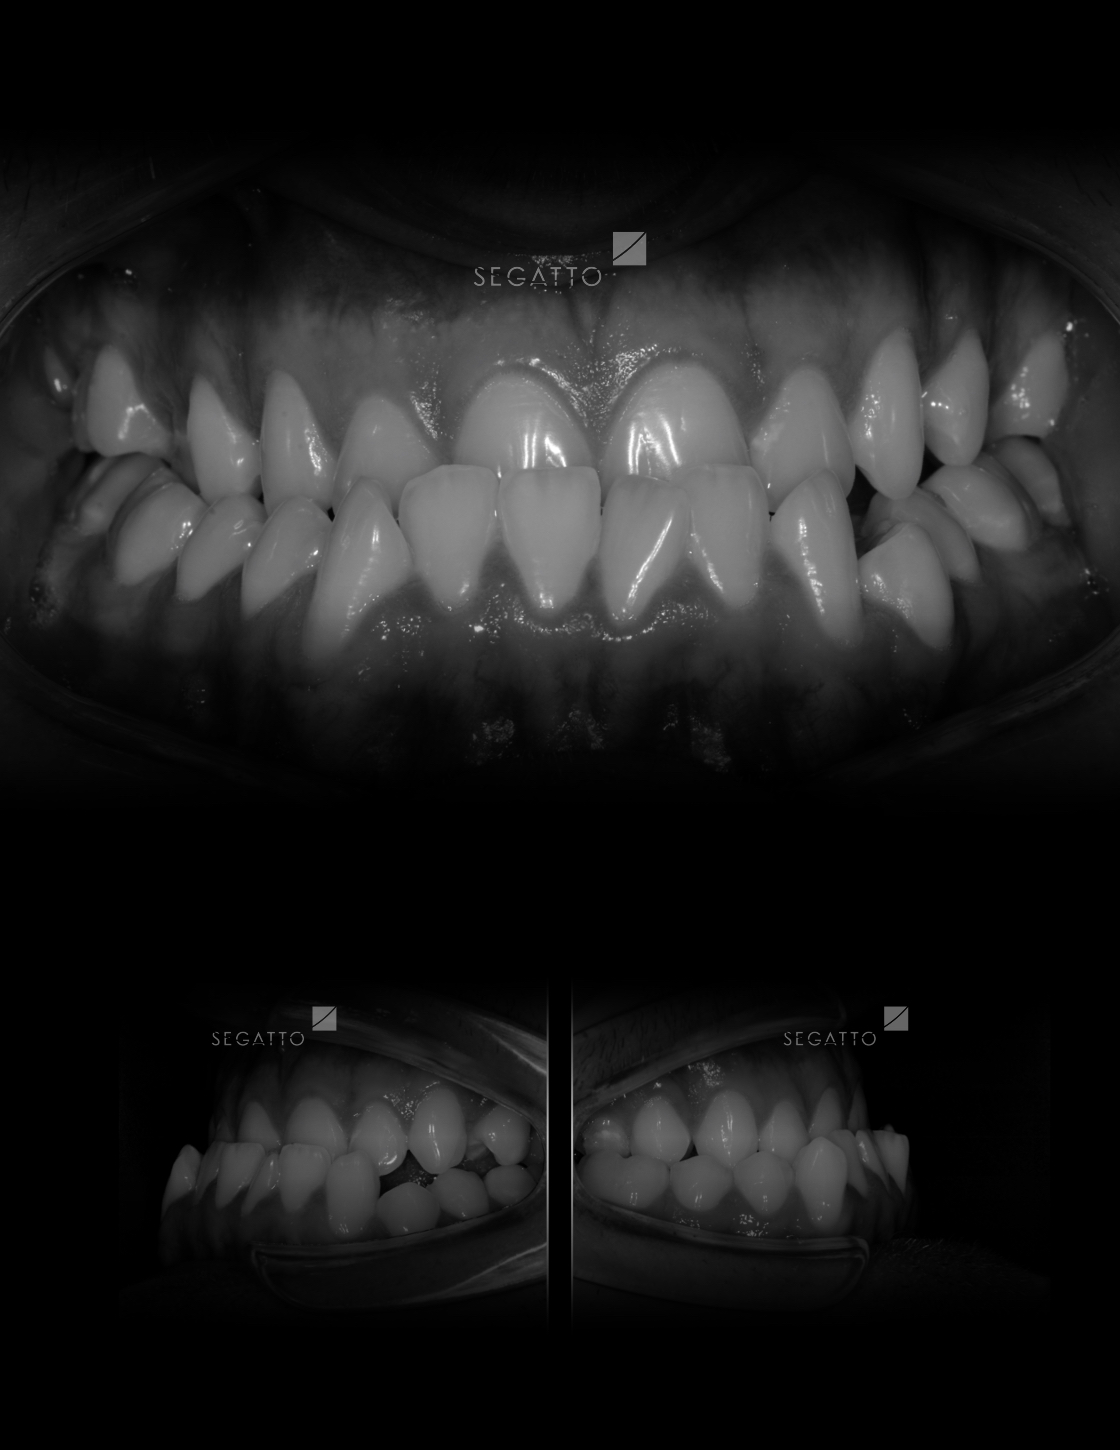

Orthodontics

Cases